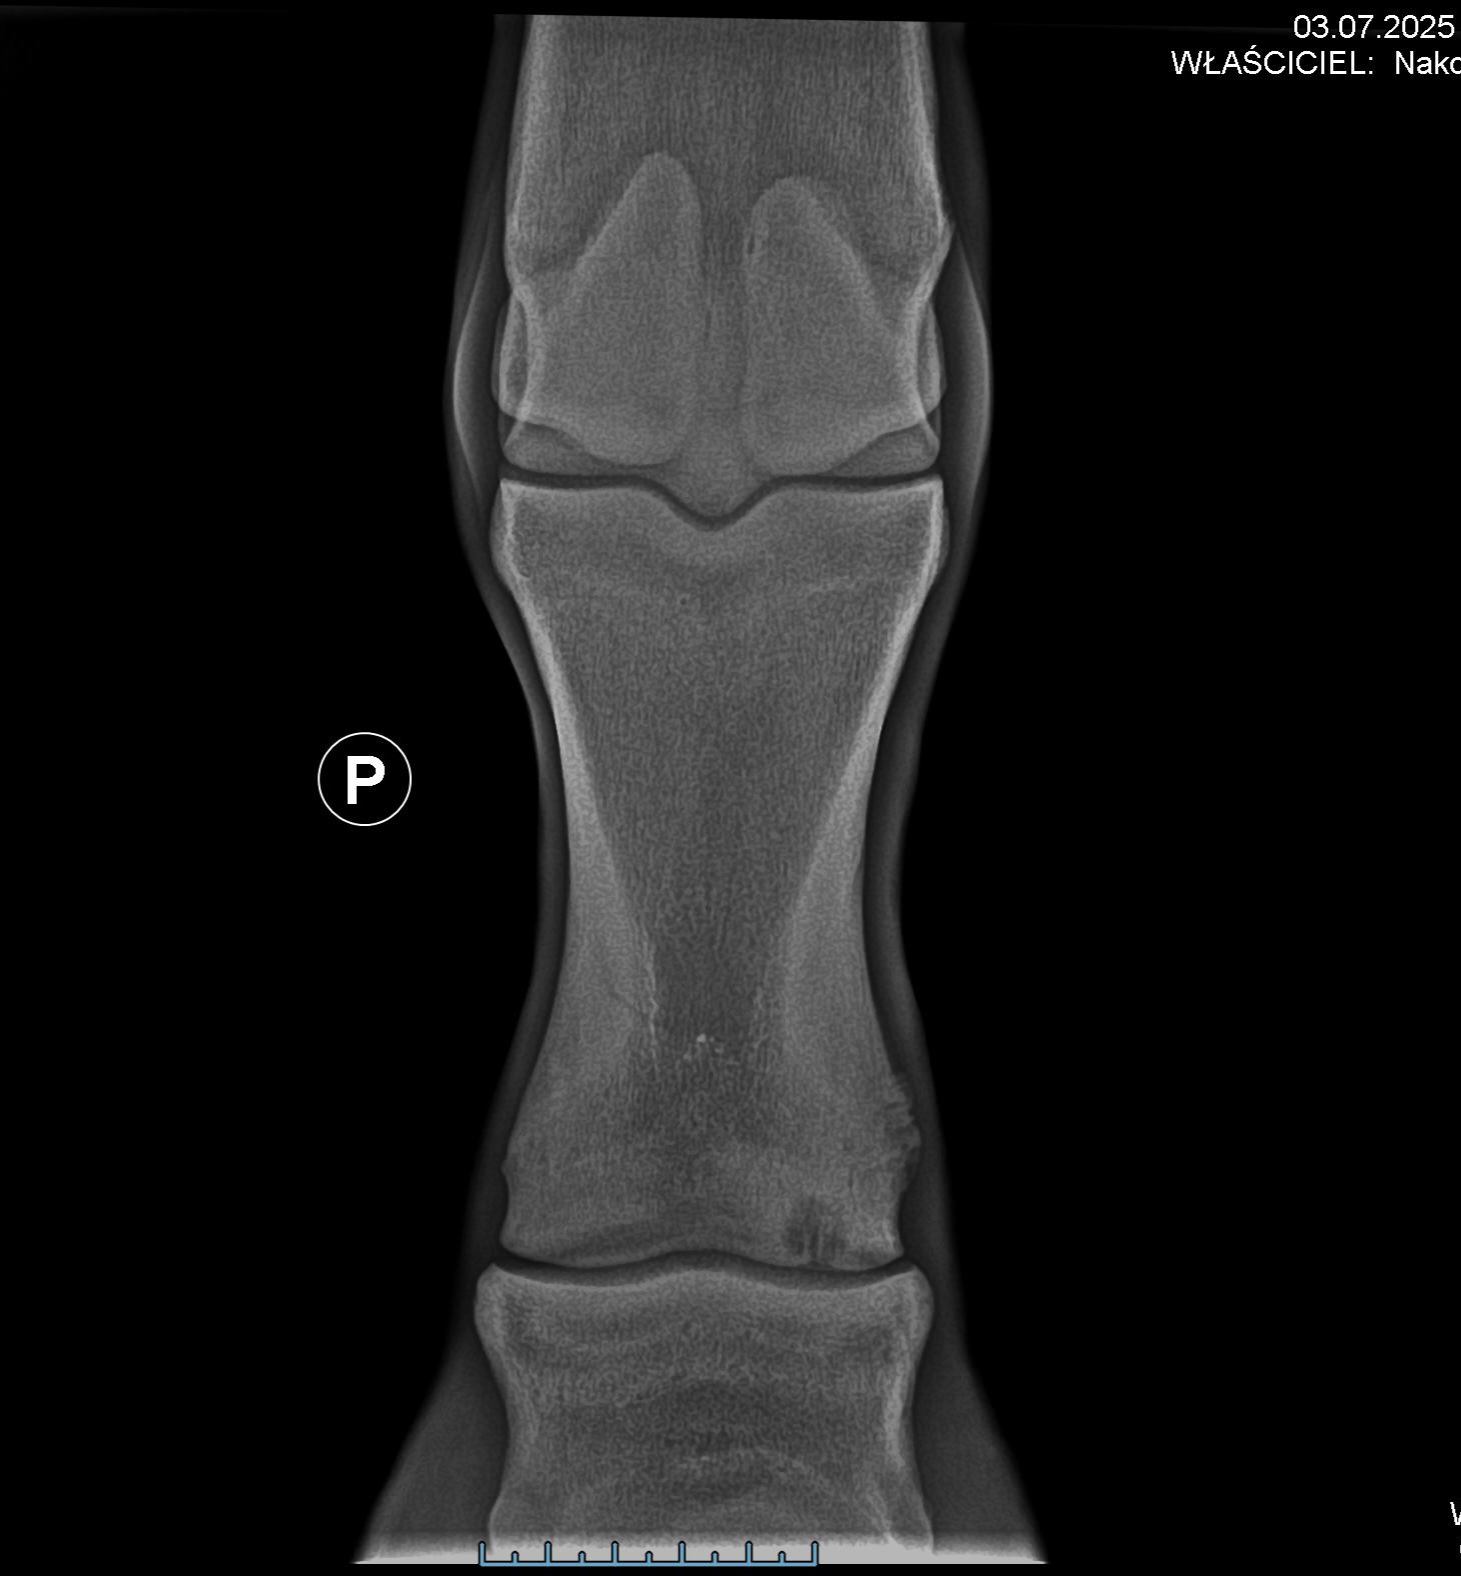

Po ostatnim skoku wzrostu Katharsis zaczęła kuleć. Z początku myślałam, że to tylko przejściowy problem związany z rozwojem. Jednak badania wykazały coś znacznie poważniejszego – podchrzęstną cystę ze szczeliną szczeliną w stawie koronowym. To wada wrodzona, która teraz, ze względu na zwiększone obciążenie podczas wzrostu, zaczęła się ujawniać i powodować ból. Bez operacji może ją czekać całe życie z bólem. W najgorszym razie – eutanazja.